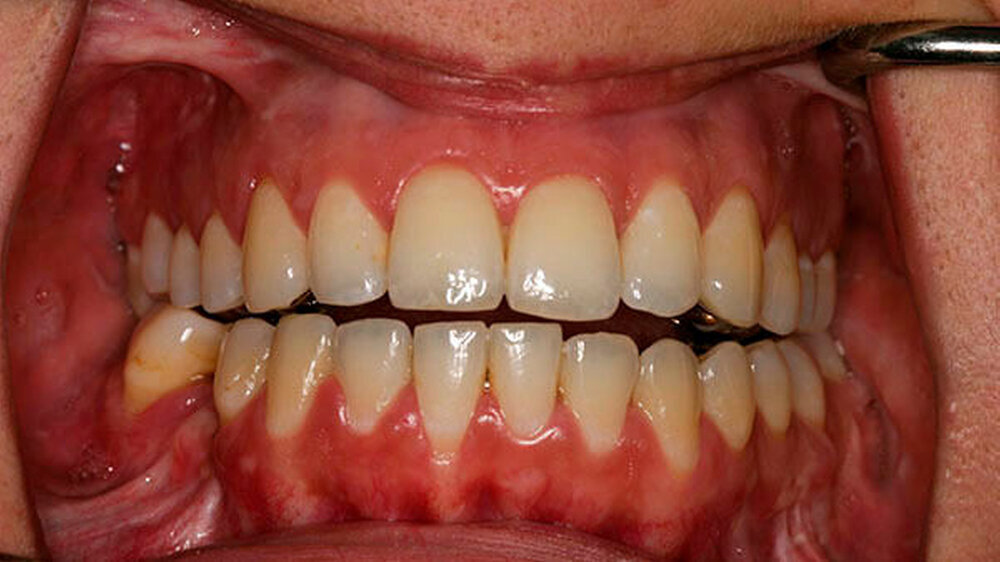

Die Patientin erreicht dauerhaft eine Mundöffnung von 35 mm ohne Schmerzen, kann jede Nahrung zu sich nehmen und hat einen stabilen Zusammenbiss der Zähne - auch die erhebliche Rücklage des Unterkiefers ist dauerhaft beseitigt.